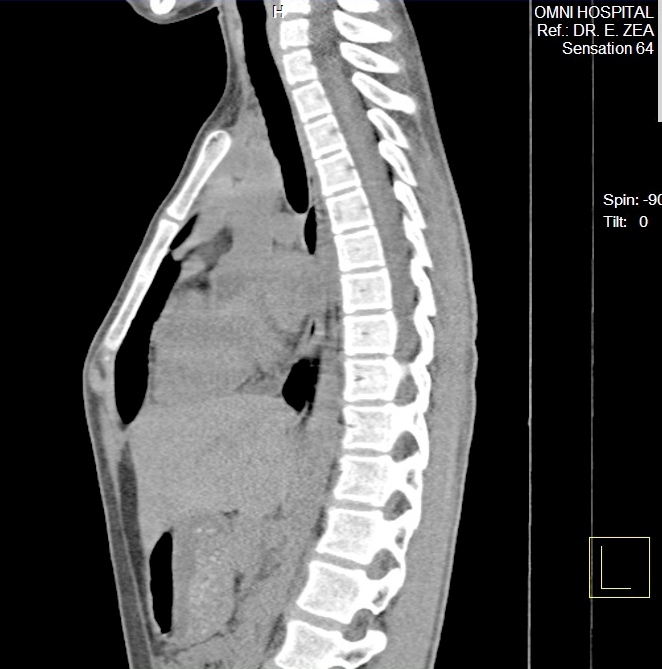

CASO 2: Hombre 10 años de edad.

Corrección quirúrgica. Operación de Abramson.

Se implantó barra metalica de compresión interna con fijación costal bilateral.